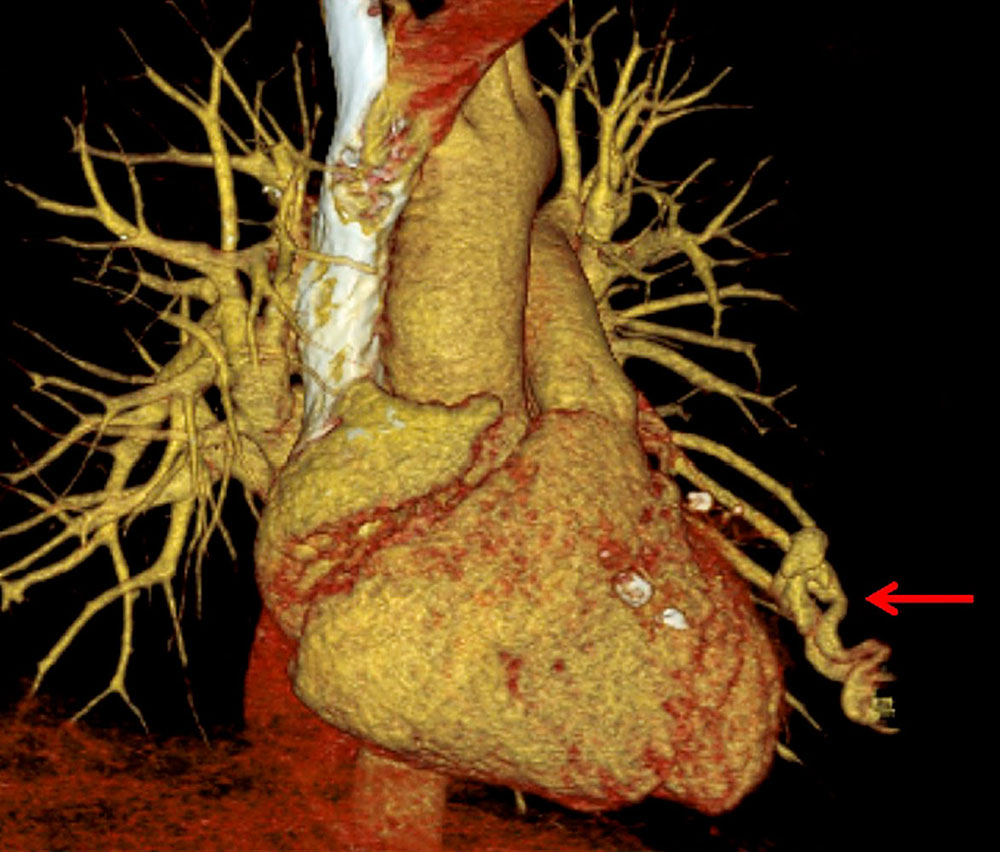

Shunts of the liver (arteriovenous, arterioportal, portosystemic) are routinely investigated by ultrasonography and, if necessary, Doppler sonography. CT, MRI, and catheter angiography complement the diagnostic workup when the suspicion of clinically relevant shunts is confirmed and the diagnosis needs to be more precise.